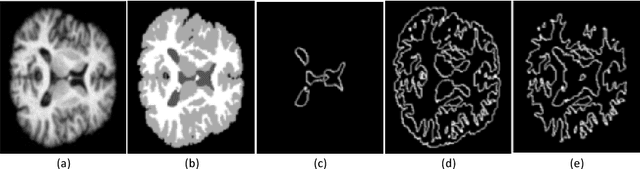

Abstract:Accurate annotation of medical image is the crucial step for image AI clinical application. However, annotating medical image will incur a great deal of annotation effort and expense due to its high complexity and needing experienced doctors. To alleviate annotation cost, some active learning methods are proposed. But such methods just cut the number of annotation candidates and do not study how many efforts the doctor will exactly take, which is not enough since even annotating a small amount of medical data will take a lot of time for the doctor. In this paper, we propose a new criterion to evaluate efforts of doctors annotating medical image. First, by coming active learning and U-shape network, we employ a suggestive annotation strategy to choose the most effective annotation candidates. Then we exploit a fine annotation platform to alleviate annotating efforts on each candidate and first utilize a new criterion to quantitatively calculate the efforts taken by doctors. In our work, we take MR brain tissue segmentation as an example to evaluate the proposed method. Extensive experiments on the well-known IBSR18 dataset and MRBrainS18 Challenge dataset show that, using proposed strategy, state-of-the-art segmentation performance can be achieved by using only 60% annotation candidates and annotation efforts can be alleviated by at least 44%, 44%, 47% on CSF, GM, WM separately.

Abstract:Accurate segmentation of brain tissue in magnetic resonance images (MRI) is a diffcult task due to different types of brain abnormalities. Using information and features from multimodal MRI including T1, T1-weighted inversion recovery (T1-IR) and T2-FLAIR and differential geometric features including the Jacobian determinant(JD) and the curl vector(CV) derived from T1 modality can result in a more accurate analysis of brain images. In this paper, we use the differential geometric information including JD and CV as image characteristics to measure the differences between different MRI images, which represent local size changes and local rotations of the brain image, and we can use them as one CNN channel with other three modalities (T1-weighted, T1-IR and T2-FLAIR) to get more accurate results of brain segmentation. We test this method on two datasets including IBSR dataset and MRBrainS datasets based on the deep voxelwise residual network, namely VoxResNet, and obtain excellent improvement over single modality or three modalities and increases average DSC(Cerebrospinal Fluid (CSF), Gray Matter (GM) and White Matter (WM)) by about 1.5% on the well-known MRBrainS18 dataset and about 2.5% on the IBSR dataset. Moreover, we discuss that one modality combined with its JD or CV information can replace the segmentation effect of three modalities, which can provide medical conveniences for doctor to diagnose because only to extract T1-modality MRI image of patients. Finally, we also compare the segmentation performance of our method in two networks, VoxResNet and U-Net network. The results show VoxResNet has a better performance than U-Net network with our method in brain MRI segmentation. We believe the proposed method can advance the performance in brain segmentation and clinical diagnosis.

Abstract:Accurate segmentation of MR brain tissue is a crucial step for diagnosis,surgical planning, and treatment of brain abnormalities. However,it is a time-consuming task to be performed by medical experts. So, automatic and reliable segmentation methods are required. How to choose appropriate training dataset from limited labeled dataset rather than the whole also has great significance in saving training time. In addition, medical data labeled is too rare and expensive to obtain extensively, so choosing appropriate unlabeled dataset instead of all the datasets to annotate, which can attain at least same performance, is also very meaningful. To solve the problem above, we design an automatic segmentation method based on U-shaped deep convolutional network and obtain excellent result with average DSC metric of 0.8610, 0.9131, 0.9003 for Cerebrospinal Fluid (CSF), Gray Matter (GM) and White Matter (WM) respectively on the well-known IBSR18 dataset. We use bootstrapping algorithm for selecting the most effective training data and get more state-of-the-art segmentation performance by using only 50% of training data. Moreover, we propose a strategy of MR brain tissue images' suggestive annotation for unlabeled medical data based on the modified U-net. The proposed method performs fast and can be used in clinical.